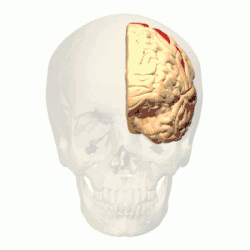

П'ять ділянок в корі головного мозку надсилають свої аксони у складі кірково-ядерного шляху. Найбільш значущою ділянкою є первинна рухова кора (поле Бродмана 4), яка знаходиться в передцентральній звивині (частина звивини, пов'язана з лицевим нервом знаходиться в нижній третині цієї звивини[2]). Іншими ділянками є допоміжна рухова кора (присередня частина поля Бродмана 6), передня премоторна кора (передня частина поля Бродмана 6), поле Бродмана 24c та поле Бродмана 23c.[52]

Якщо ураження (наприклад, інсульт) виникає в корі нижньої частини передцентральної звивини чи в кірково-ядерному шляху, то розвивається центральний параліч лицевого нерва — патологія, яка проявляється зникненням можливості рухати мімічними м'язами нижньої частини обличчя на протилежному до ураження боці, в той час, як рухливість м'язів верхньої частини обличчя збережена. Окрім синдромів, які уражають власне систему лицевого нерва, тут описано ряд розладів, пов'язаних з екстрапірамідною системою. Порушення в корі головного мозку може проявлятися дисоціацією свідомих та несвідомих мімічних рухів. Наприклад, при ураженні лобної частки головного мозку пацієнт при своєму бажанні може підняти кутик рота. Однак, цього не відбуватиметься, коли він буде сміятися. Протилежна ситуація виникає при ураженні нижньої третини передцентральної звивини чи волокон кірково-ядерного шляху[77].